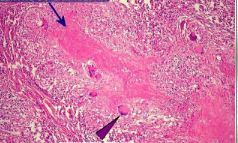

LEPTOMENINGITE TUBERCULOSA : GRANULOMAS INCIPIENTES, NECROSE CASEOSA E VASCULITE NECROSANTE [exemplo de inflamação granulomatosa]

ENDARTERITE AGUDA : EXSUDATO FIBRINO-LEUCOCITÁRIO ENTRE O ENDOTÉLIO E A MÉDIA [exemplo de inflamação granulomatosa]